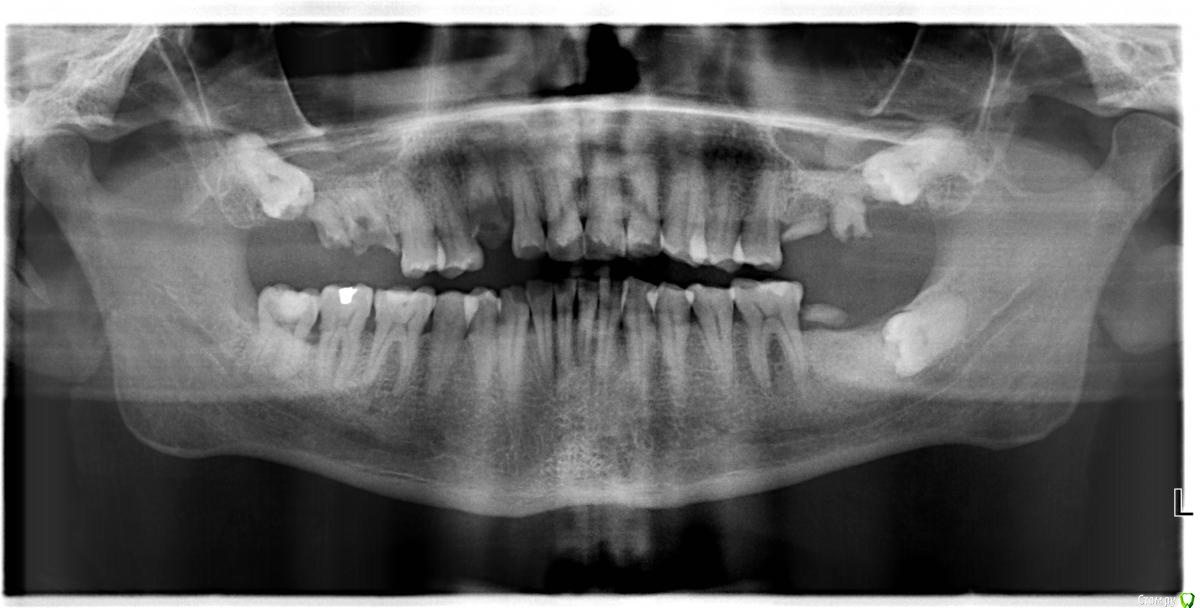

Михалыч007 Опубликовано 29 октября, 2016 Поделиться Опубликовано 29 октября, 2016 Всем доброго времени суток.Как говориться:хочется,могу,но надо ли?Суть в том ,что планируется имплантация в проекции зуба 37.Вроде и ретенированный 38 далеко.Можно ли его оставить? У кого какой опыт в подобных ситауциях? Учитывая ,то что впереди много удалений,костных пластик и прочее,не хотел бы лишнюю травму для пациента... Ссылка на комментарий

Astronaft Опубликовано 3 ноября, 2016 Поделиться Опубликовано 3 ноября, 2016 Я не сторонник удалять все подряд, но здесь бы умеренно рекомендовал удалить.- КПУ у пациента высокий- скорее всего было сообщение с полость рта = какой-то карман с бактериями- на рентгене подозрение на окклюзионный кариес- удаление не тяжелое, риск/травма минимальныеЗачем хранить этот очаг? Пациента мягко склонял бы к полной санации, которая включает гигиену и удаление. 1 Ссылка на комментарий

Irouil Опубликовано 3 ноября, 2016 Поделиться Опубликовано 3 ноября, 2016 Надо смотреть КТ, но создается впечатление что 3.8 укрыт надкостницей (минимум). Если так, то удалять не вижу смысла. Как тут уже писали выше - коронку на винте и рентген контроль раз в 6-12 месяцев. Если все же прободает бугром в мягкие ткани поверхностнее надкостницы и/или есть намек на кариес на жевалке (снимок намекает) - удалять. Ссылка на комментарий